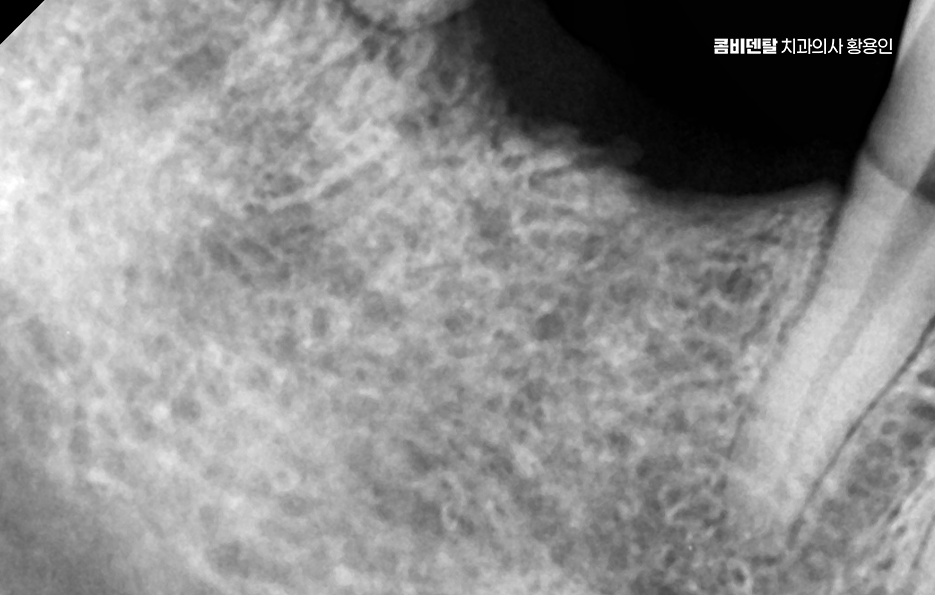

또 치아가 없어진 자리는 잇몸 뼈가 점점 흡수되면서 꺼지게 되는데, 그 결과 얼굴이 비대칭으로 보이거나 추후에는 임플란트를 하려고 해도 부족한 잇몸 뼈로 인해 뼈이식과 같은 치료를 추가적으로 받아야 할 수 있었어요

치아 발치 후 임플란트 치료 과정은 처음에 CT나 파노라마 엑스레이를 통해 뼈의 양과 밀도, 신경 위치를 정확히 확인하는 것부터 시작되며 치아가 빠진 자리에 뼈가 많이 흡수되어 있다면, 임플란트를 심기 전에 뼈이식을 먼저 해야 할 수 있지만 반대로 뼈 상태가 좋다면 임플란트를 심고, 보통 3개월 동안 뼈와 잘 붙을 때까지 골융합 과정을 기다리게 되며 골융합이 잘 이루어진 뒤에는 그 위에 지대주라는 연결 부품을 끼우고, 그 위에 최종 보철물을 씌우면서 치료가 마무리되고 있어요